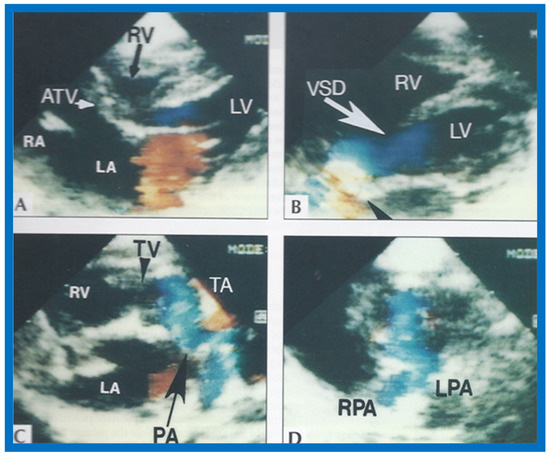

Following the demonstration of the atretic tricuspid valve, the sizes of the cardiac chambers were evaluated both by M-mode (Z scores) and 2D echocardiography; enlarged RA, LA and LV, and a small RV, were seen (Figure 14, Figure 15, Figure 16 and Figure 17). Pulsed (not shown) and color Doppler (Figure 19) studies were helpful in illustrating the right-to-left shunt across the patent foramen ovale or atrial septal defect. Contrast study using agitated saline with 2D imaging clearly demonstrated successive opacification of the RA, LA, LV and then the RV in that order, but such a study is not necessary for diagnosis.

The relationship of the great arteries is examined next in order to classify them into various types [41]. The relationship of the great arteries is established by following the vessels arising from the ventricles until pulmonary bifurcation or aortic arch. In Type I patients with normally related great arteries, the aorta arises from the LV (Figure 20), while in Type II patients with transposition of the great arteries, the PA arises from the LV (Figure 21 and Figure 22). In Type III patients, it may be little more difficult to assign the great artery relationship, and sometimes angiography is needed. In type IV with truncus arteriosus, the limited data [22] suggest that this can be done by echocardiography (Figure 23 and Figure 24).

Figure 20.

Selected video frames from precordial long axis views of a neonate with tricuspid atresia with normally related great arteries demonstrating enlarged left atrium (LA) and left ventricle (LV), a small right ventricle (RV) and a moderate sized ventricular septal defect (VSD) (thick arrow) on 2D (A) and color flow (B) imaging. Turbulent flow (B) with a Doppler flow velocity of 2.91 m/s by continuous wave Doppler (C) suggests some restriction of the VSD. Ao, Aorta; PA, pulmonary artery. Reproduced from Rao P.S. [39].

Figure 21.

(A) Selected video frame from precordial long axis views of a neonate with tricuspid atresia and transposition of the great arteries demonstrating the left atrium (LA), left ventricle (LV), a very small right ventricle (RV) and a moderate sized ventricular septal defect (not marked). The vessel coming off of the LV is traced in (B) and shown to bifurcate into left (LPA) and right (RPA) pulmonary arteries, confirming that this is the main pulmonary artery (MPA). Ao, Aorta. Reproduced from Rao P.S. [39].

Figure 22.

Selected video frame from precordial long axis view with color flow mapping of another neonate with tricuspid atresia and transposition of the great arteries illustrates the left atrium (LA), left ventricle (LV), a small right ventricle (RV) and a moderate sized ventricular septal defect (VSD). The vessel coming off of the LV bifurcates into left (LPA) and right (RPA) pulmonary arteries. Reproduced from Rao P.S. [39].

Video frame from a two-dimensional echocardiographic and color Doppler study demonstrating (A) atretic tricuspid valve (ATV) between the right atrium (RA) and right ventricle (RV) and blood flow from the left atrium (LA) into the left ventricle (LV) across the mitral valve. The RV (arrow) is very small and hypoplastic. (B) LV and RV with a large ventricular septal defect (VSD) below the truncus arteriosus (TA). Turbulent flow across the truncal valve suggests truncal valve stenosis. (C) origin of the pulmonary artery (PA) from the TA by color flow (arrow), and (D) division of right (RPA) and left (LPA) pulmonary arteries from the PA (labeled in d) in a short-axis view. TV, truncal valve leaflets. Reproduced from Rao P.S., et al. [22].

Then, the ventricular septum is evaluated; the ventricular septum is intact in most Type Ia cases. In children with Type I (normally related great arteries), the VSD supplies pulmonary blood flow (Figure 20) while in patients with Type II (transposition the great arteries), the VSD allows blood to flow into the systemic circuit (Figure 21 and Figure 22). In Type I patients, the VSD is demonstrated by 2D (Figure 20A) and the left to-right shunt across it by color (Figure 20B), pulsed and CW (Figure 20C) Doppler signals. Interrogation of the right ventricular outflow tract and pulmonary artery region is performed; peak Doppler flow velocity across the right ventricular outflow tract and pulmonary valve is helpful in identifying obstruction across these sites. The Doppler data from the VSD and RVOT are also helpful in estimating of pulmonary artery pressures. In these Type I babies, the 2D size of the VSD and the peak Doppler flow velocity across it are useful in quantifying the size of the VSD (Figure 20); the higher the VSD Doppler velocity, the smaller the defect. However, in patients with pulmonary hypertension, severe infundibular or valvar pulmonary stenosis, the VSD Doppler velocities do not reflect the size of the VSD. Barring these exceptions, right ventricular and pulmonary arterial pressure may be estimated using modified Bernoulli equation (RV/PA systolic pressure = systolic BP − 4V2).

In Type II patients, the VSD may be small, causing obstruction to blood flow to the systemic circuit; therefore, the size of the VSD should be ascertained by 2D (Figure 21 and Figure 22), color Doppler (Figure 22), pulsed (Figure 25) and CW Doppler, as necessary. In these Type II patients, the high VSD velocity is indicative of subaortic obstruction. Interrogation of left ventricular outflow and PA region may reveal pulmonary or subpulmonary stenosis; the higher the velocity, the more severe the obstruction. Study from suprasternal notch may show aortic coarctation (Figure 26), which is not uncommon in patients with the Type II anatomy.